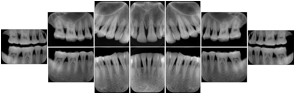

Intra-oral radiography typically involves acquisition of multiple images of various parts of the dentition. Many digital radiographic systems offer customized templates that are used for displaying the images in a study on the screen. These templates may also be referred to as mounts or view sets. The Structured Display Object represents a standard method of encoding and exchanging the layout and intended display of Structured Displays. A structured display object created in this manner could be stored with a study and exchanged with images to allow for complete reproduction of the original exam.

In most standard cases, images are oriented in structured layouts. These structured displays are useful to be shared between providers for reference purposes.